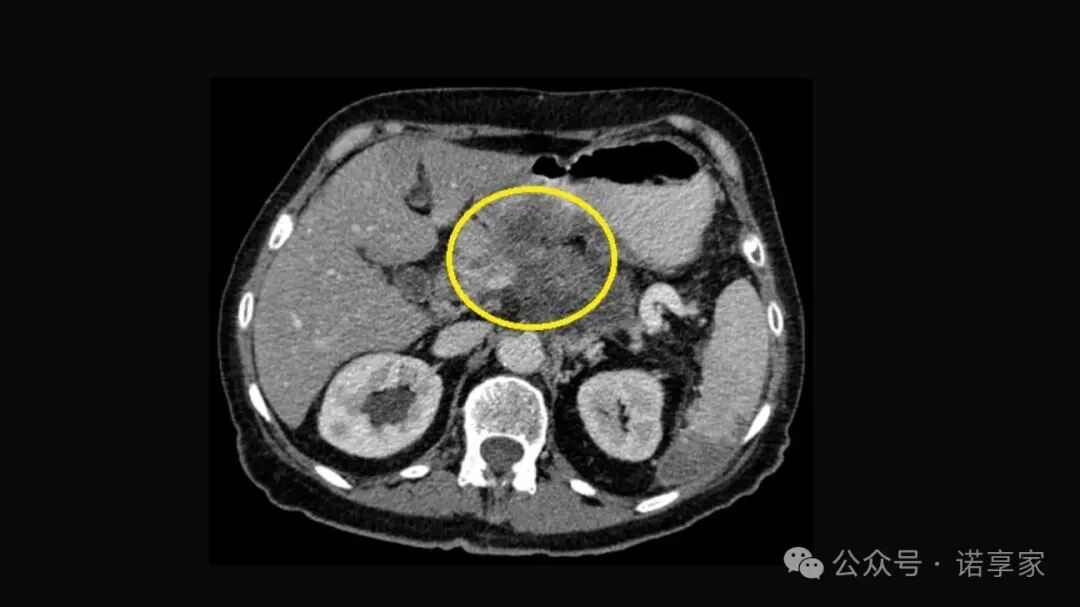

🔍 1. 胰腺增强CT(多期)

观察肿块、血管侵犯、转移

是基础检查,但对非常早期病灶仍可能看不清